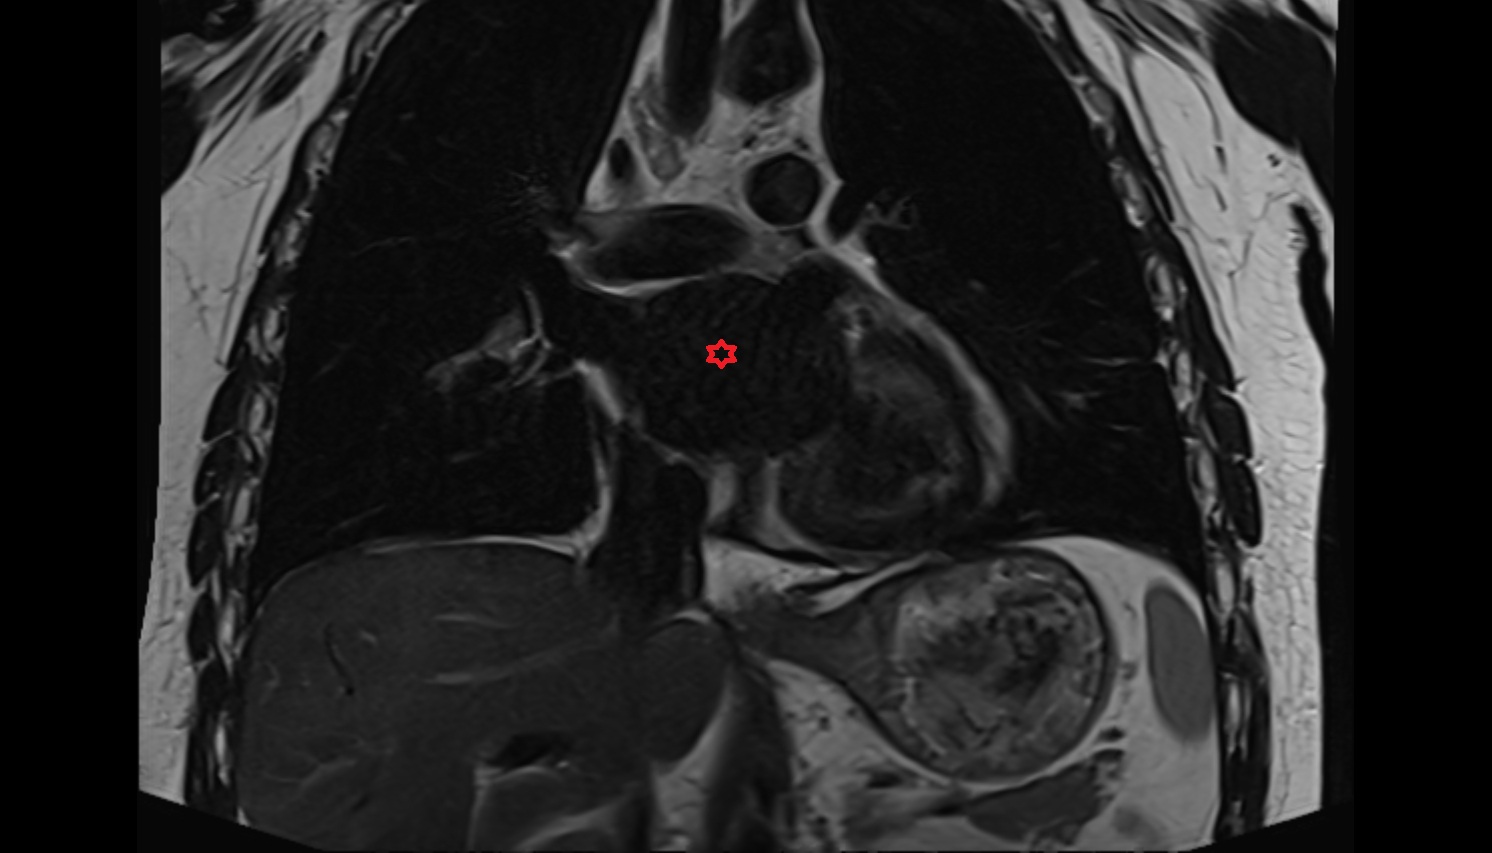

- Heart

- Left ventricle

- Right atrium

- Left atrium

- Right ventricle